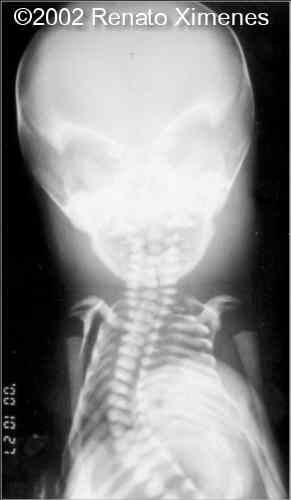

The baby and radiograms

case0072-11

case0072-12